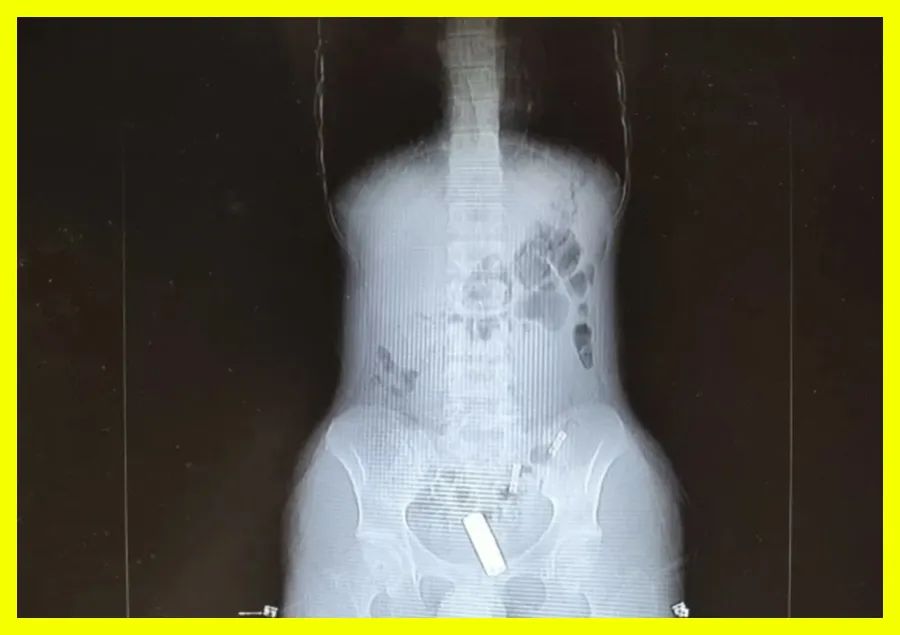

21岁的大学男生“小包”,将一节5号电池用纸巾包裹后,塞入了自己的“菊部”。可无法取出,狂喝水一天后也没排出,于是就到了杭州市中医院就诊。

由于已经过去了一天,拍片后发现,电池已经卡在了第一个肠袢。

虽然电池体积不大,但是电池中的重金属含有剧毒,一旦破损会对人体造成无法挽回的后果!

因此直肠肛门的形态是上大下小,上松下紧的结构。当强行有异物进入后,括约肌会收缩恢复到紧闭状态,阻止异物轻易排出。

过程中,异物很容易就到达了直肠。直肠名叫直肠,其实是弯曲的,大大增加了取出异物的难度。